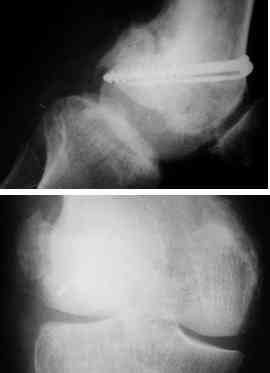

This 20 year old patient sustained a fracture in the lower end of the femur, one and a half years ago, with a compound wound over the fracture area. Notes at that time mention a compound fracture dislocation, with a loss of part of the lateral condyle. This was treated by debridement, and external fixation. After two weeks, the lateral condyle (coronal fracture) was fixed by a screw and k wire in an AP direction.

At present, he has a valgus deformity of the knee, with 0-45 degrees of movt. The knee is stable to examination, could not be corrected to neutral from the existing valgus, and despite the deformity he is walking on it, albeit with pain and some difficulty.

I cannot make certain from the AP whether the screw and KW are still present. The lateral however shows that the lateral condyle was fixed with disregard to the bone defect. So it was proximally displaced in relation to the medial condyle with the resultant valgus. I would do an open wedge osteotomy with bone graft and internal fixation. However, this would require a precise estimate of the correction angle and placement of the fixation device. I would use a DCS.